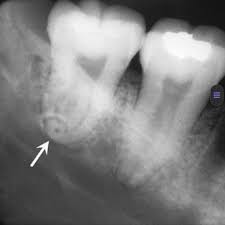

Hạt trai men

Là phần men răng có dạng như ngọc trai, kích thước từ 1 – 2 mm, thường xuất hiện hơi phía trên vùng chẽ các răng cối lớn, tỉ lệ ở hàm trên cao gấp 7 lần hàm dưới.

Hạt trai men không chứa tủy răng. Chúng có thể góp phần gây viêm nha chu mãn tính và gây cản trở thao tác của các dụng cụ nha chu.